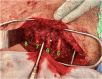

Figure 8.

Tendon grafts passed through drill holes and tied around medial scapula & plate.